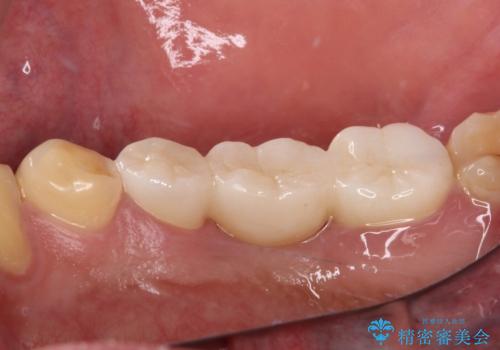

抜歯部分の治癒を待つ間に、全体的な汚れの多さを改善する指導と処置を進め、その後オールセラミックブリッジにて補綴治療を行うこととしました。

神経を取り除く可能性のあった奥歯ですが、何とか保存することができました。

奥歯はしっかりと治療することができたので、今後は虫歯予防と他の要治療歯の処置を行っていくことになります。